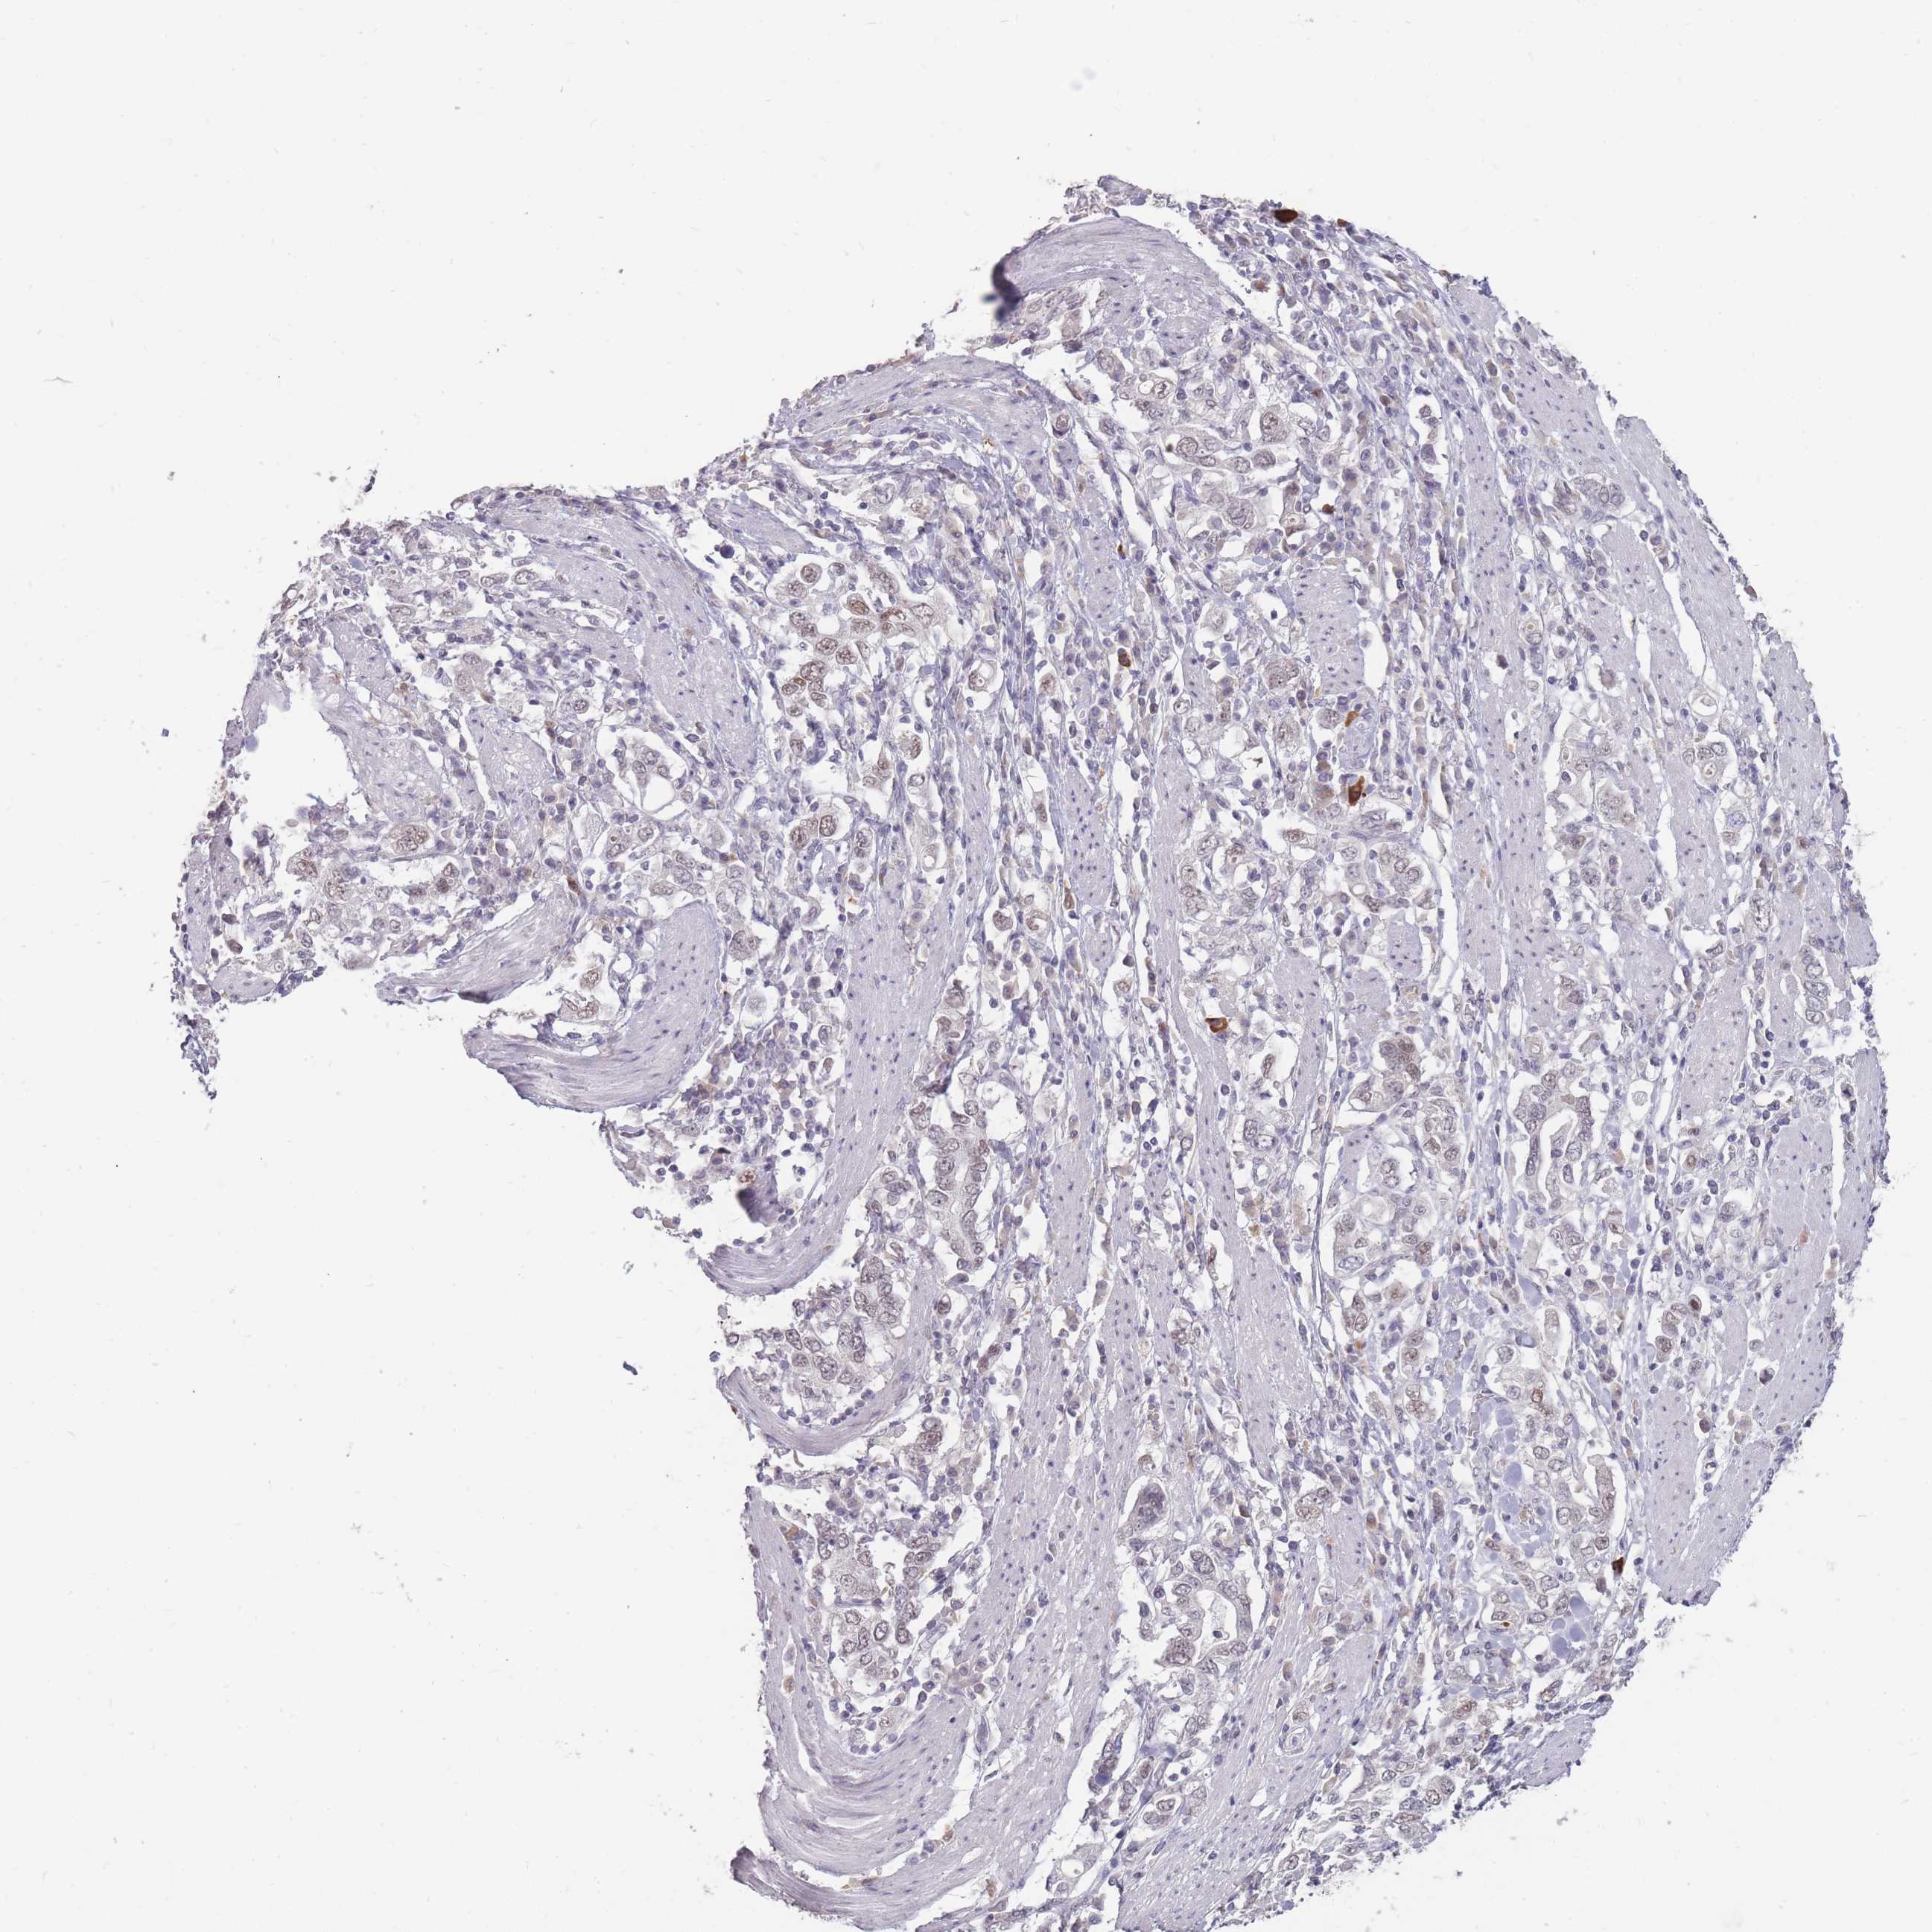

STOMACH CANCER - Protein expressioni

A mouse-over function shows sample information and annotation data. Click on an image to view it in a full screen mode. Samples can be filtered based on level of antibody staining by selecting one or several of the following categories: high, medium, low and not detected. The assay and annotation is described here.

Note that samples used for immunohistochemistry by the Human Protein Atlas do not correspond to samples in the TCGA dataset.

Antibody stainingi

Antibody staining in the annotated cell types in the current human tissue is reported as not detected, low, medium, or high, based on conventional immunohistochemistry profiling in selected tissues. This score is based on the combination of the staining intensity and fraction of stained cells.

Each image is clickable and will lead to virtual microscopy that enables deeper exploration of all samples and also displays staining intensity scores, fraction scores and subcellular localization as well as patient and tissue information for each sample.

Antibody HPA046290

Antibody HPA049475

Antibody CAB046477

Staining

High

Medium

Low

Not detected

Intensity

Strong

Moderate

Weak

Negative

Quantity

>75%

75%-25%

<25%

None

Location

Nuclear

Cytoplasmic/membranous

Cytoplasmic/membranous,nuclear

Adenocarcinoma, NOS